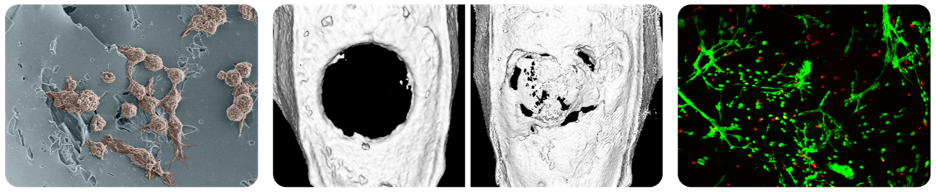

Our lab seeks to develop biomaterial and therapeutic delivery systems that specifically respond to cell-generated signals. These next-generation, "smart" material systems enable us to engineer comprehensive regeneration of damaged or diseased tissues.

The Bioresponsive Materials Lab seeks to develop new technologies for orchestrating regeneration of diseased or damaged tissues. Current regenerative systems primarily rely on 1) material implants whose biodegradation rates can drastically diverge from the pace of new tissue formation, and 2) poorly controlled pharmaceutic delivery that incompletely recapitulate natural healing processes. Consequently, there remains a need for regenerative medicine platforms that can selectively release therapeutics and biodegrade in response to localized, cell-specific healing responses.

Therefore, our group explores bioresponsive, "smart" material systems that leverage precise, cell-generated signals (including presence of reactive oxygen species, pH changes, and enzymatic activity) to activate biomaterial functionality and guide tissue regeneration.